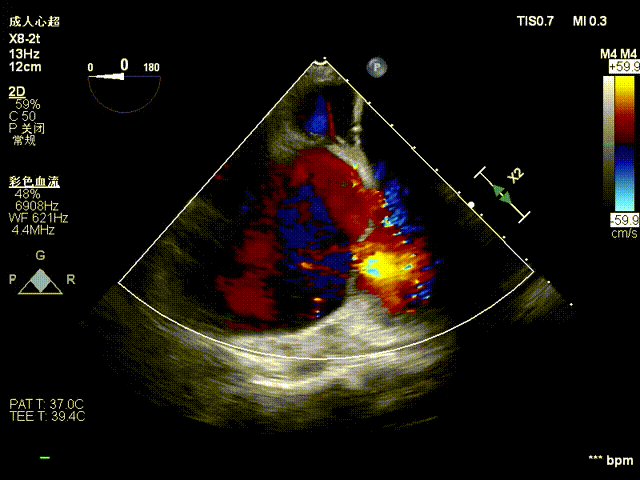

图3.术前超声

图5.术后超声

手术在全麻状态下进行,郭惠明教授团队采用经右侧颈静脉入路的方式送入输送器进入体内,并在TEE和DSA的指引下进行。在输送器进入右室后释放室间隔锚定装置,旋转输送器,使得锚定装置对准室间隔面;而后释放前瓣夹持件,确定夹持件位于右室侧释放LuX-Valve Plus人工瓣膜盘片,再使用DSA和超声确认盘片是否位于右房侧,同时调整瓣膜的同轴性。紧接着在DSA和超声的监视下调整室间隔锚定件贴合室间隔,释放室间隔锚定装置。再次确认瓣膜的稳定性和同轴性后,将输送器撤出体内,最终完成LuX-Valve Plus人工瓣膜植入(图2-5),手术获得圆满成功。患者在手术室即刻拔除气管插管,术后超声提示LuX-Valve Plus人工三尖瓣瓣膜同轴性良好,瓣架固定牢靠,无反流和瓣周漏。